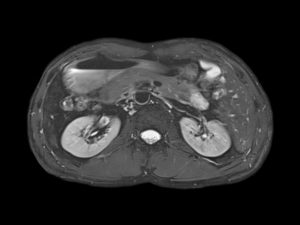

МРТ – магнитно-резонансная томография, суть проведения которой заключается в сканировании, с помощью сильного магнитного поля. Исследование способом МРТ позволяет считать всю характеристику объекта в деталях. При этом, длительность процедуры в среднем составляет 30-40 мин.

Она безопасна для человека, не вызывает структурные изменения тканей, поэтому список противопоказаний относительно небольшой. С помощью МРТ можно одновременно просканировать разные органы, отследить причину воспаления или поражения мочевыделительной системы. Отсутствие боли или неприятных последствий при уникальном качестве также считается преимуществом способа диагностики.

- МРТ соединяет свойства электромагнитного поля. Оно передает информацию в виде высокочастотных импульсов, которые компьютер считывает в виде четких срезов толщиной не более 1–2 мм. Последние модели сканеров формируют трехмерное изображение почки с прилегающими кровеносными сосудами, что необходимо при сложных операциях, трансплантации.

МРТ почек — это визуализационный метод исследования, который базируется на использовании магнитных полей высокой, средней и низкой напряженности.

Магнитно-резонансная томография лучше визуализирует мягкие ткани: мышцы, мозг, печень.